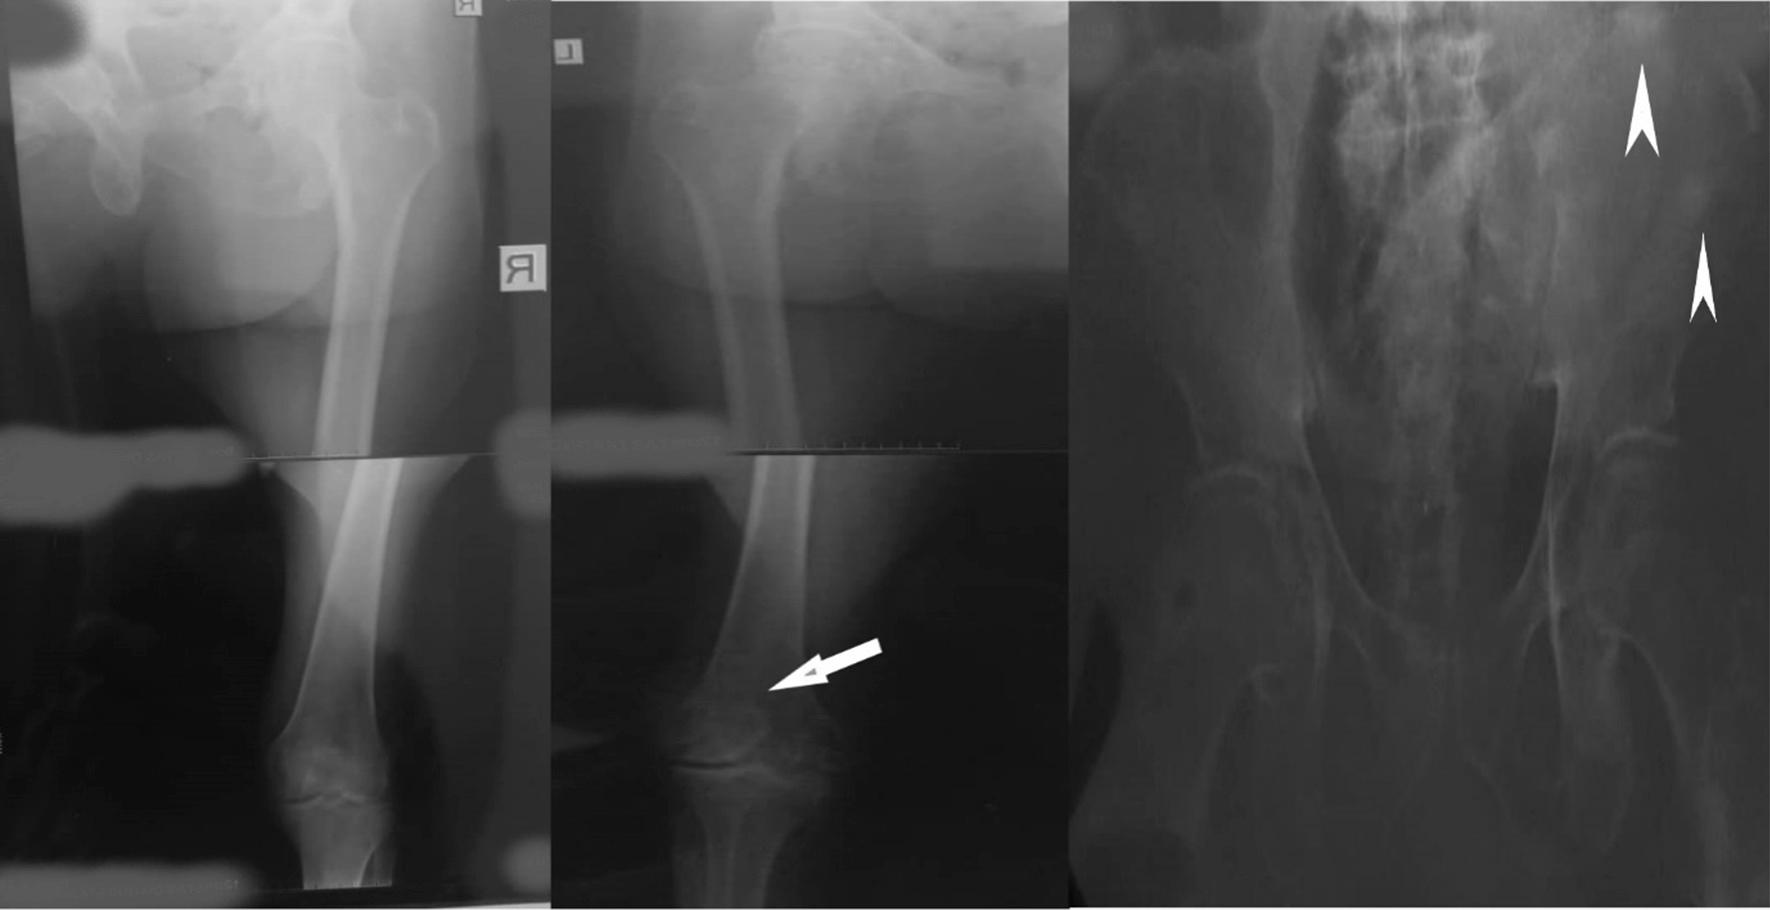

A 71-year-old Nigerian man, who presented at our hospital with 1-month-old complaints of inability to walk together with low back and bilateral thigh pains. This presentation had been preceded by a 5-month history of lower urinary tract symptoms. On examination, the prostate was hard and nodular as were the left testis and spermatic cord. On histological assessment of a needle biopsy, prostatic adenocarcinoma (Gleason score 5 + 5 = 10) was diagnosed. A subsequent therapeutic bilateral total orchidectomy specimen was found to contain metastatic prostatic carcinoma deposits, in the testes, epididymides, and spermatic cords. Although our patient is currently doing well postoperatively on zoledronic acid, ketoconazole, bicalutamide, and tamsulosin, he is being re-evaluated periodically for any feature of recurrence.

一名71岁的尼日利亚男性,因1个月来无法行走以及腰背部和双侧大腿疼痛前来我院就诊。在此之前有5个月的下尿路症状病史。检查时,前列腺坚硬且呈结节状,左侧睾丸和精索也是如此。经针吸活检的组织学评估,诊断为前列腺腺癌( Gleason评分5 + 5 = 10)。随后的双侧治疗性睾丸切除术标本发现睾丸、附睾和精索中有转移性前列腺癌沉积物。尽管我们的患者目前在接受唑来膦酸、酮康唑、比卡鲁胺和坦索罗辛治疗后术后情况良好,但仍在定期重新评估是否有复发迹象。